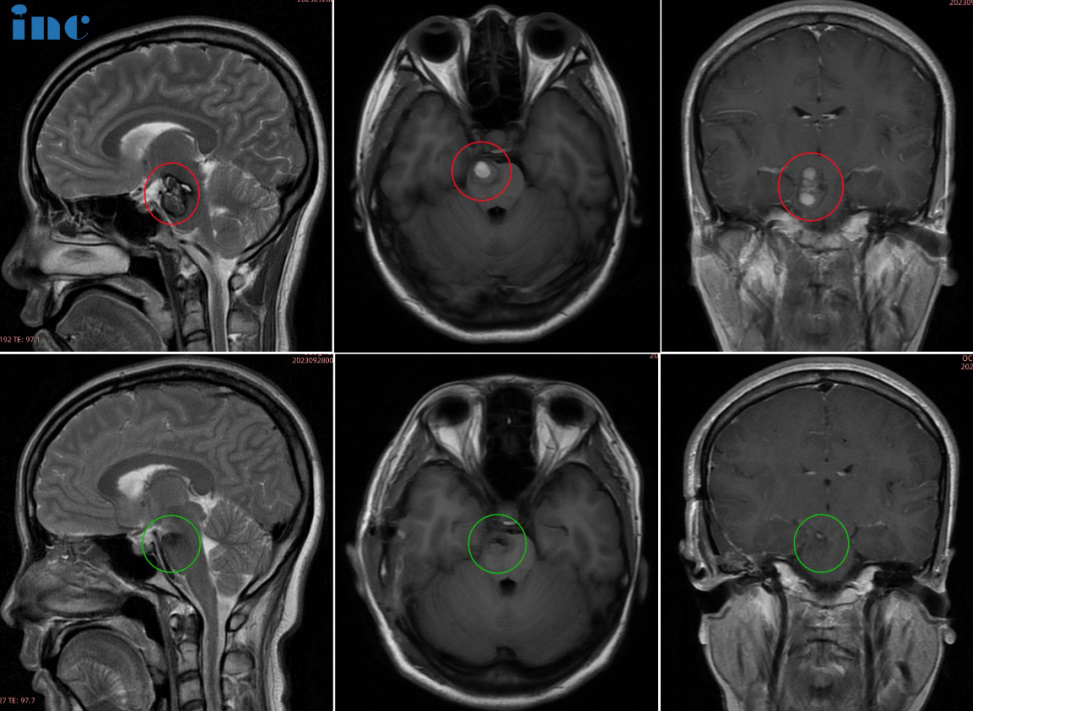

巴教授6月中國行期間,一位68歲右側(cè)基底節(jié)占位-海綿狀血管瘤的柯女士通過INC咨詢來到巴教授蘇州獨墅湖醫(yī)院咨詢室。“癥狀主要還是從頭部、胳膊到后背,腿一直到腳底麻的感覺,偶爾臉部也會麻木……復(fù)查時發(fā)現(xiàn)病灶變大了,原來是18*19mm,現(xiàn)在是24*19mm;而且還多次血。”因癥狀加重,病灶增大,問診多名神經(jīng)外科醫(yī)生,兩個專家團(tuán)隊醫(yī)生給出了截然不同的意見:不贊成手術(shù)治療,理由是年齡大,手術(shù)導(dǎo)致癱瘓失語的風(fēng)險大。另外一個醫(yī)生團(tuán)隊的意見是現(xiàn)在可以馬上手術(shù),但效果不確定。因此柯女士至今尚未進(jìn)行治療。而咨詢巴教授之后,教授給出了的評估。在手術(shù)決策上,巴教授偏向手術(shù),在手術(shù)風(fēng)險上,教授表示有把握。

68歲女性柯女士——基底節(jié)海綿狀血管瘤

柯女士和家人商量后原本想要等巴教授下一次來華時再進(jìn)行手術(shù),然而誰也沒想到9月底教授在華手術(shù)期間柯女士癥狀開始出現(xiàn)波動,發(fā)作頻繁,當(dāng)巴教授查看核磁圖像后,發(fā)現(xiàn)病灶較前增大,結(jié)合患者病情有進(jìn)展,告知患者隨時會有出血風(fēng)險,需要立即手術(shù)??屡亢图胰伺c巴教授緊急視頻溝通之后,決定提前手術(shù),果斷買飛機(jī)票來到蘇州。手術(shù)成功,柯女士一家人終于松了一口氣,這個困擾他們已久的問題終于得到的解決。

術(shù)后情況

術(shù)后核磁顯示,海綿狀血管瘤得到順利全切,柯女士的狀態(tài)也好,神采奕奕,和常人無異。術(shù)后2天巴教授查房時,已經(jīng)可以下地走路。看到前來查房的巴教授,柯女士激動,親切擁抱感謝巴教授,終于擺脫了危險的基底節(jié)海綿狀血管瘤的她滿懷感激得握住巴教授的手說道,“我要看看巴教授這雙神奇的大手,這是上帝之手,巴教授感謝你!”